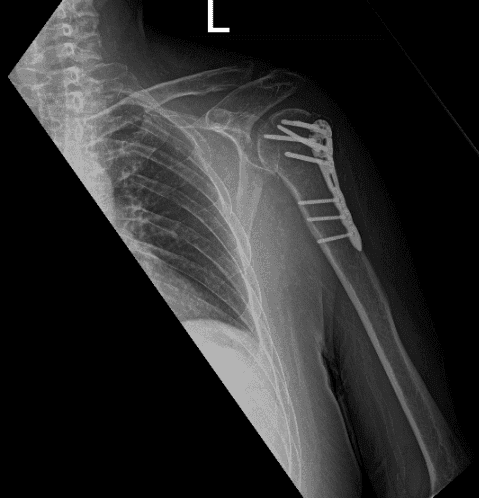

Xray reviewed- found surgically treated comminuted fracture of the humeral head and neck. By this time, we agreed to start Physical therapy.

Post-operative X-ray.

The patient is in status post-surgical repair of a comminuted fracture of the humeral head and neck. Fracture fragments are in good position and alignment. The surgical hardware is intact.

Patient last visit is 8 weeks after the operation, clearly seen on his X-ray that he is doing well with his surgery.